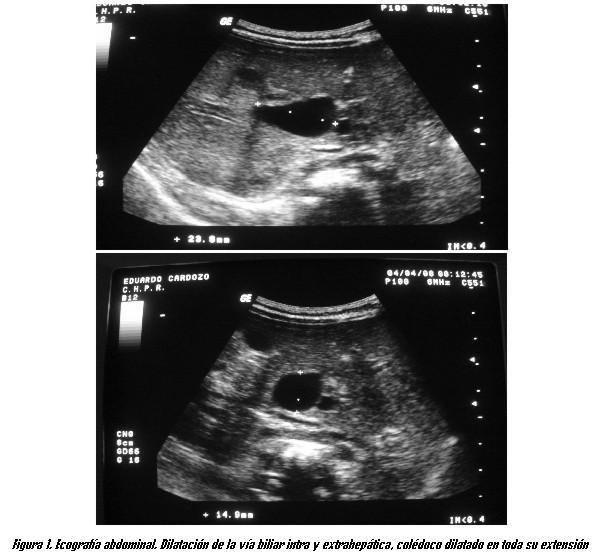

La ecografía abdominal mostró dilatación de la vía biliar principal, con un colédoco dilatado en toda su extensión, con diámetro máximo en el sector medio de 12 mm. El sector distal del colédoco se visualizó con dificultad, aunque podría estar dilatado. Podría corresponder a un QC fusiforme tipo Ib. El parénquima hepático era normal, así como el resto de la cavidad abdominal (figura 1). Se realizó una colangio-resonancia que mostró un QC tipo Ib, sin compromiso de la confluencia de los hepáticos ni del colédoco distal (figura 2).

Para la investigación de estas patologías se solicitó una ecografía, técnica de primera línea que permite valorar anomalías anatómicas del hígado y la vía biliar extrahepática. El estudio confirmó la presencia de un QC. La ecografía tiene 92 a 97% de especificidad para el diagnóstico de las malformaciones quísticas de la vía biliar (2,13,14,19). Permite el diagnóstico diferencial con atresia de vías biliares en el neonato (16). También es útil en el diagnóstico prenatal del QC, aunque en estos casos es difícil la diferenciación con atresia de vía biliar (8).